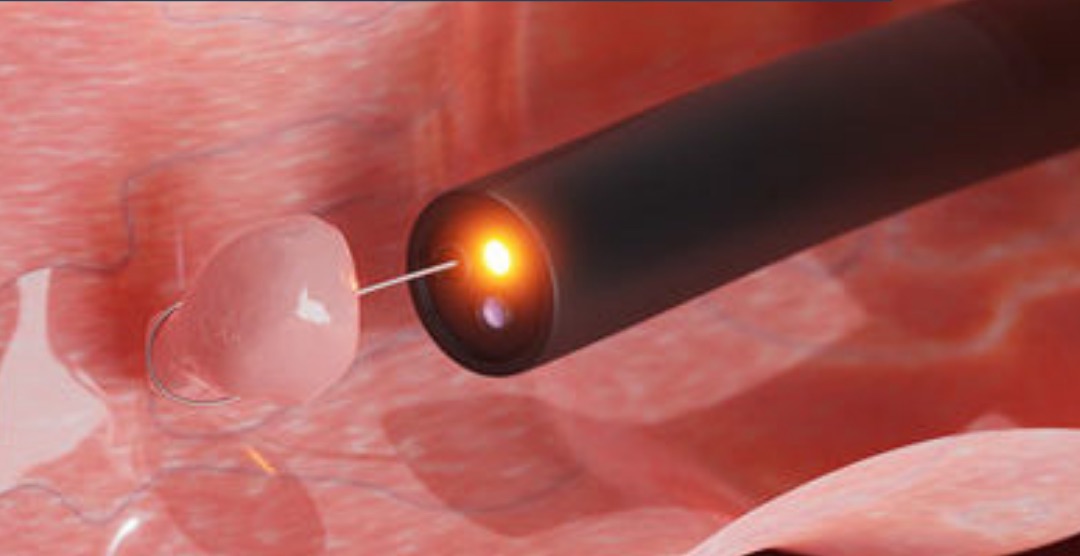

- Histeroscopía diagnóstica (método de elección)

La histeroscopía permite visualizar directamente la cavidad uterina y evaluar el grado de las adherencias.

Sí. El tratamiento es quirúrgico y mínimamente invasivo:

- 🔬 Histeroscopía quirúrgica, para liberar las adherencias

- Código 2001005: Histeroscopía diagnóstica.

✔️ Histeroscopía diagnóstica y quirúrgica